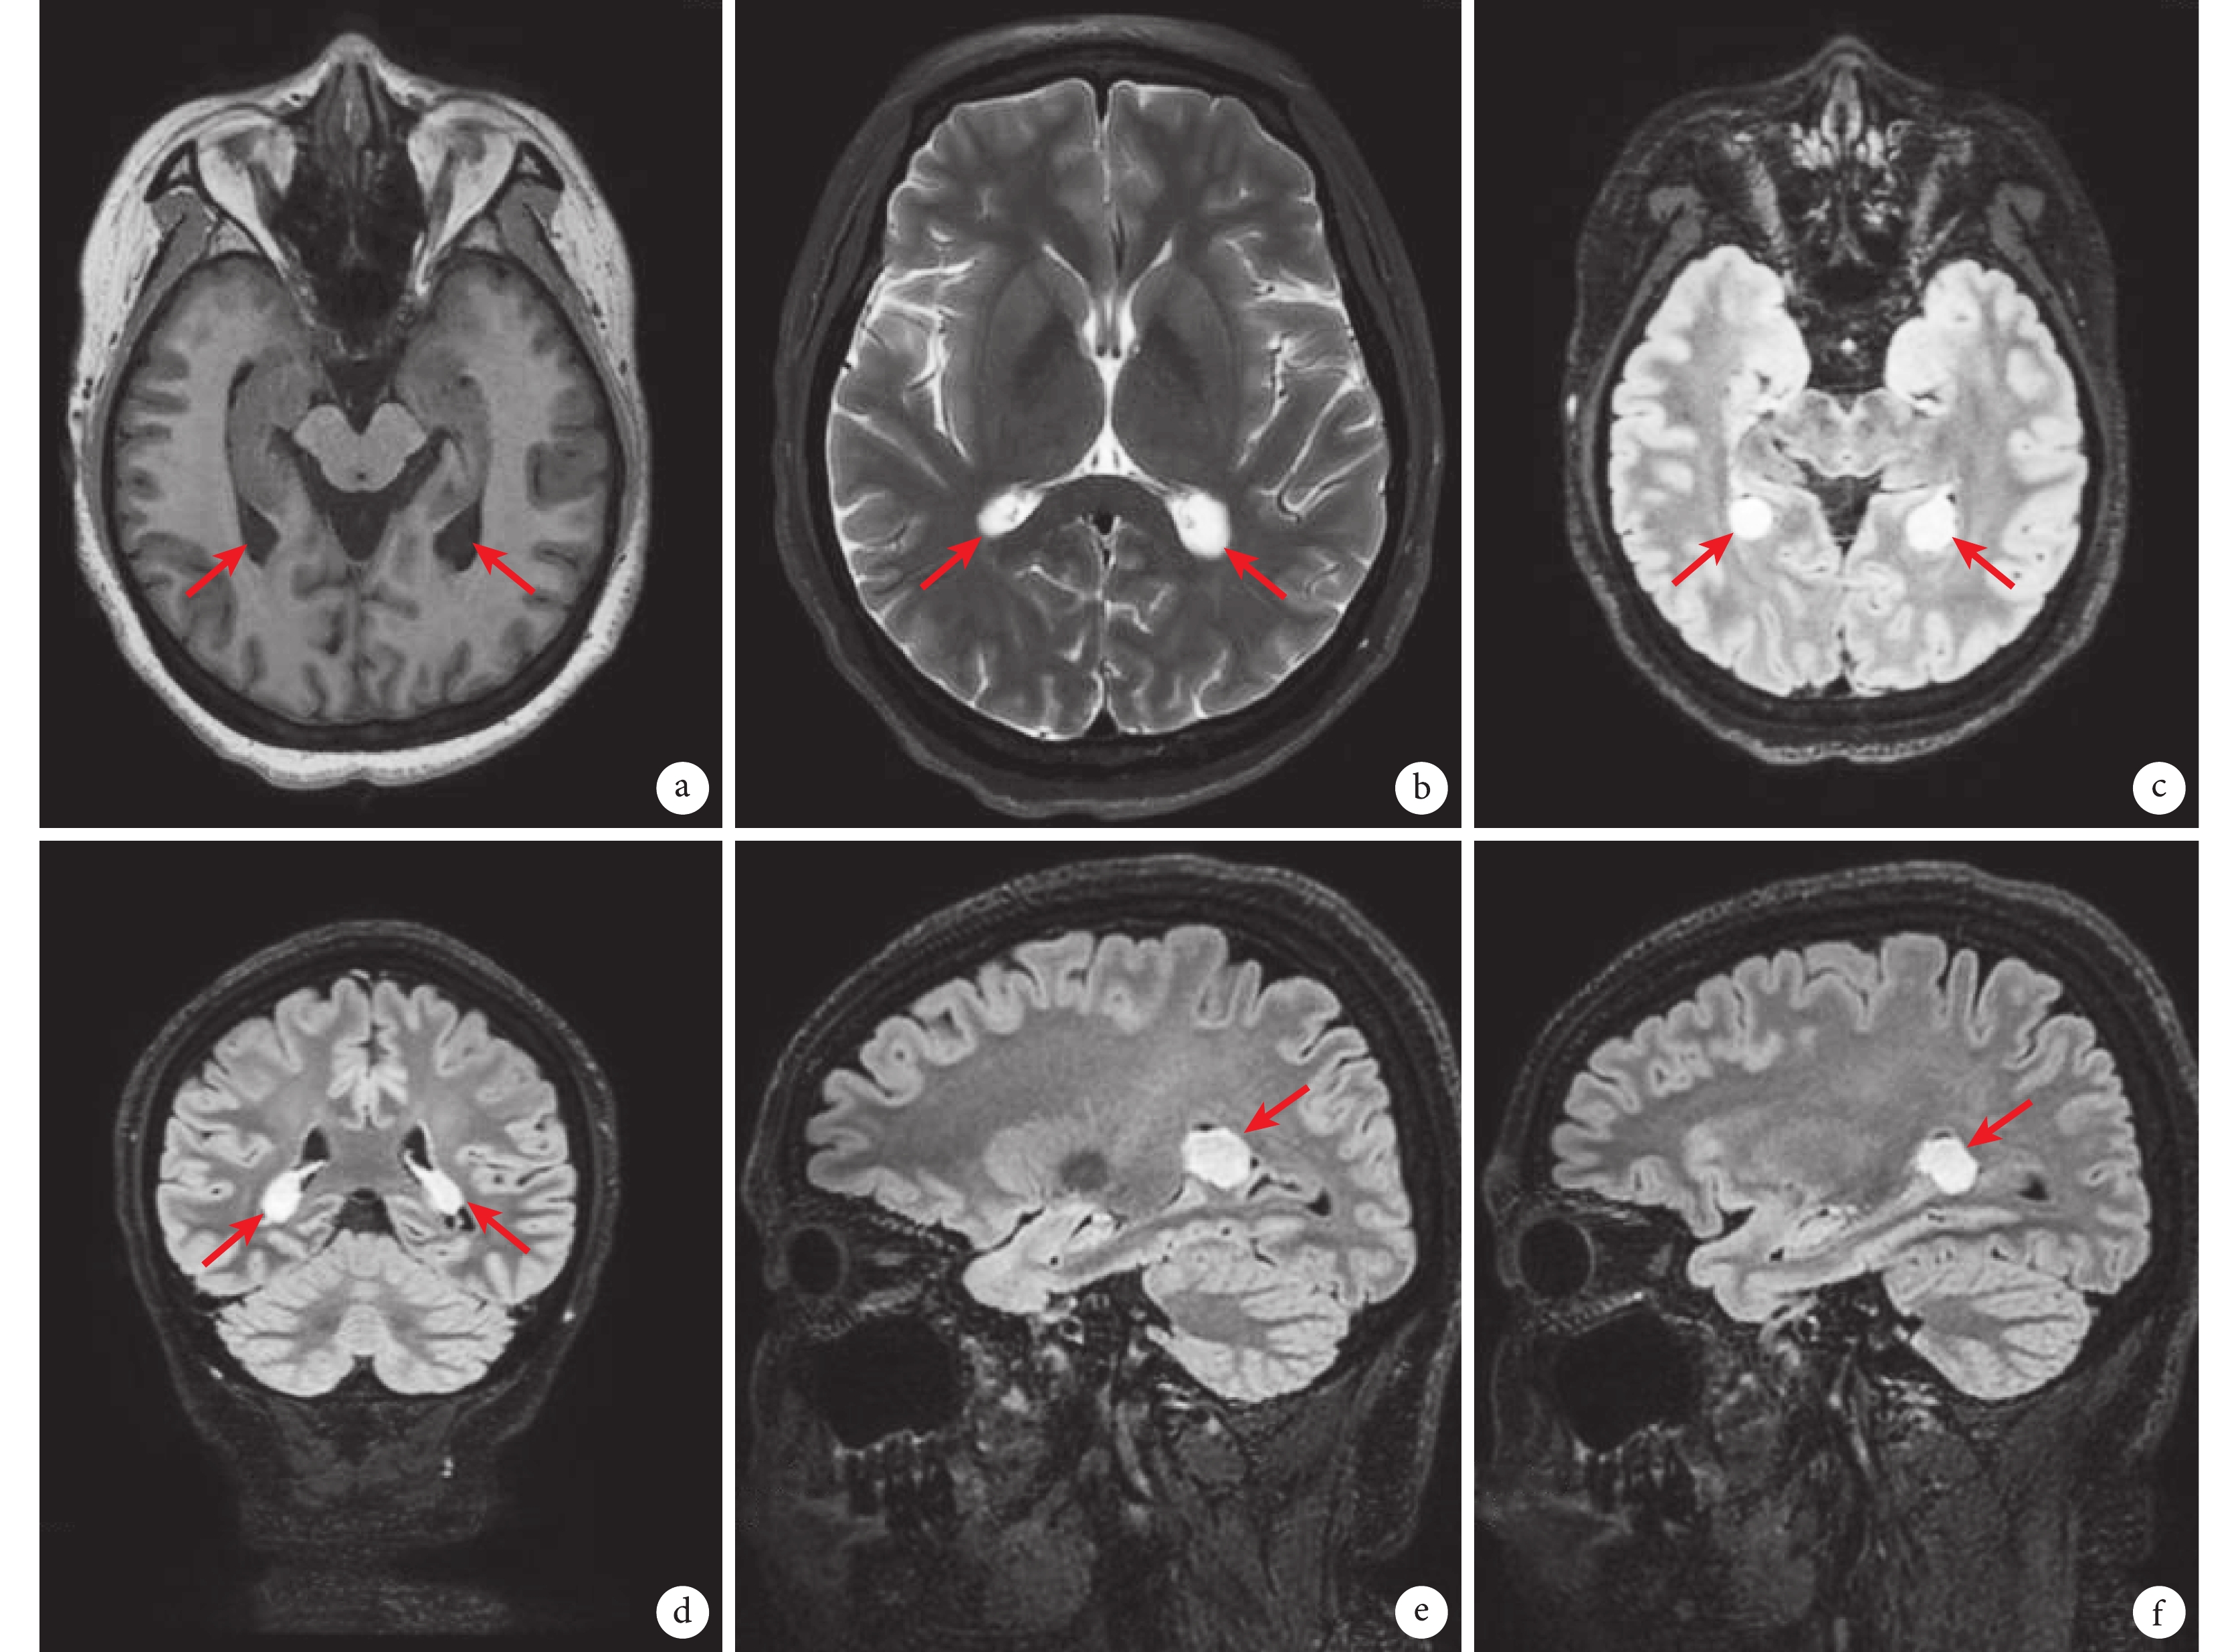

a. 橫軸面T1WI示雙側側腦室三角區結節影,呈較低信號(箭頭所示);b. 橫軸面T2WI示病灶呈高信號(箭頭所示);c. 橫軸面T2-FLAIR示病灶呈高信號(箭頭所示);d. 冠狀面T2-FLAIR示病灶高信號(箭頭所示);e. 矢狀面T2-FLAIR(示右側腦室)示右側病灶呈高信號(箭頭所示);f. 矢狀面T2-FLAIR(示左側腦室)示左側病灶呈高信號(箭頭所示)